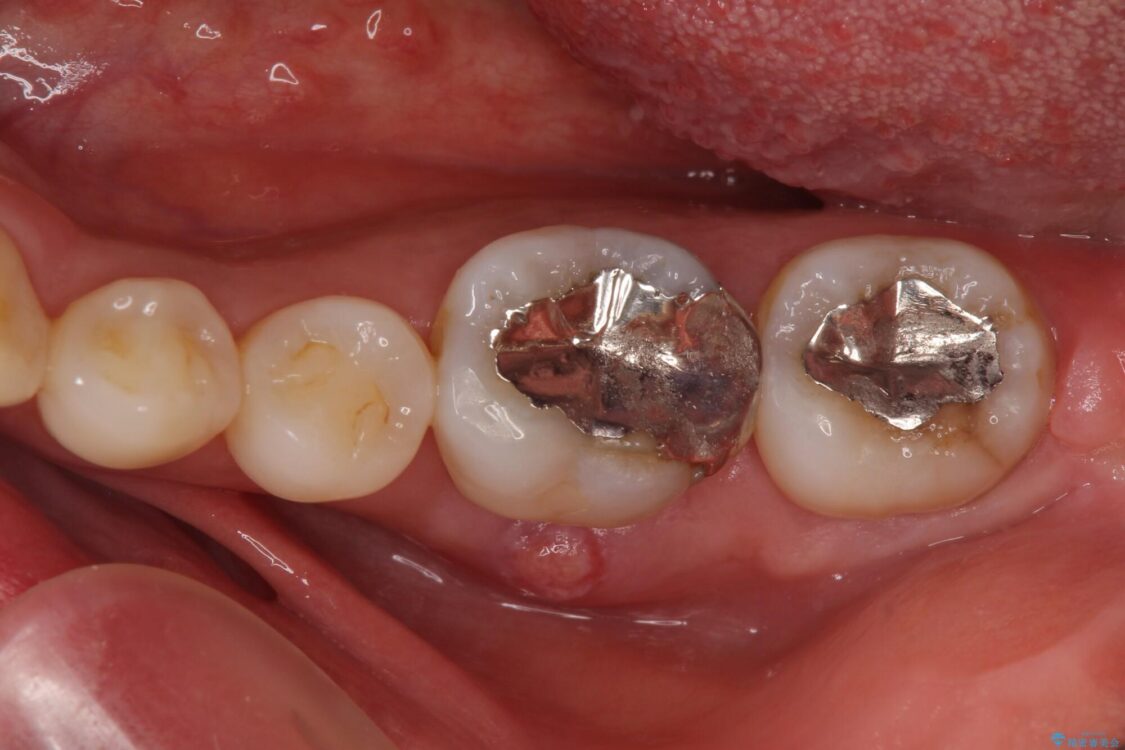

以前むし歯治療をした後から定期的に痛むことがあるとのことで、レントゲン写真より神経組織が失活していることが予想されました。

銀歯を外すと神経組織の一部が取り除かれており、歯根に付け根に穴が空けられている状態でした。

• むし歯で歯茎から血が出てくる オールセラミッククラウンでの補綴治療 治療前画像